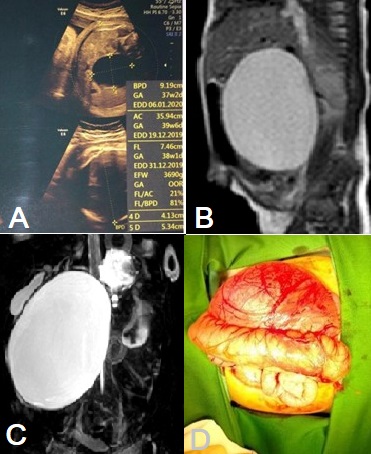

Prenatal ultrasonography (US) in the third trimester showed an anechoic cyst with a size of 5.5x4.7x4.7cm (Fig. 1A). Magnetic Resonance Imaging (MRI) done on the 4th day of life showed a cyst in the right upper quadrant with a clear and smooth border, with a size of 5.33x5.99x7.10cm, compressing the gallbladder, porta-hepatis, pancreas, gaster, duodenum, small intestine, and ascending colon (Fig. 1B). The Magnetic Resonance Cholangiopancreatography (MRCP) performed showed dilated right and left intrahepatic bile ducts, suspecting a choledochal cyst, Todani type 1 (Fig. 1C).

Due to persistent vomiting a decision to operate the CC early was taken. An open cyst excision and Roux-en-Y hepaticojejunostomy were done on the 7th day of life. A CC with a size of 5x5x7cm was excised and a normal-sized gallbladder was found intraoperatively (Fig. 1D). The cyst was compressing the duodenum, which correlated with clinical symptoms. The patient was discharged 15 days after surgery. After nine months of observation at the outpatient clinic, the patient is doing fine.

A) Antenatal scan showing a cyst, B) MRI showing a hyperintense cyst. C) MRCP showing CC type 1. D) Operative picture showing a huge cyst.